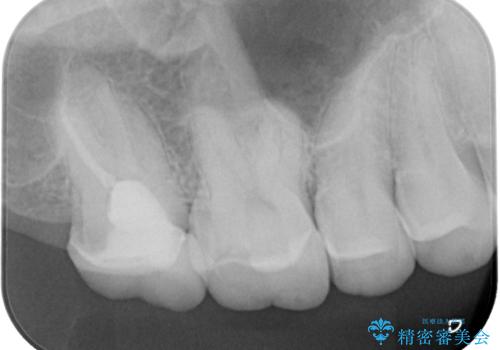

- 奥歯の被せものが欠けたとのことで来院された患者様です。上の奥歯なので機能面や強度を優先しPGAクラウン(ゴールドクラウン)のご提案をしましたが、セラミックの被せものがよいとのことでオールセラミッククラウンによる補綴治療を行っていくことにしました。

拡大鏡視野下で古い被せものを除去し、オールセラミッククラウンに適した形に整えました。

歯と歯茎の間に圧排糸と言われる糸を入れてシリコーン印象材にて型どりをしました。

患者様のご希望により、根管治療、土台のやり替えは行っていません。